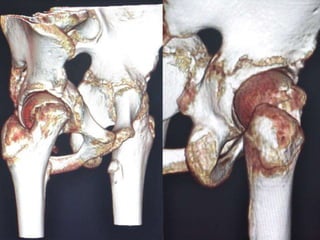

 CT SCAN-

Accurately measures extent of epiphyseal displacement & angulation.

FEMOROACETABULAR IMPINGEMENT